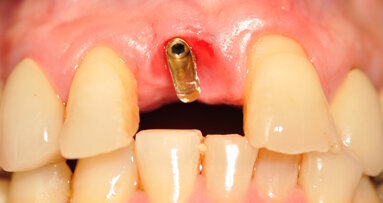

La paziente è stata sottoposta a profilassi antibiotica tramite somministrazione di 2 g di amoxicillina/acido clavulanico (Augmentin, GlaxoSmithKline) un’ora prima della chirurgia. La paziente inoltre ha eseguito sciacqui orali con clorexidina 0,2% (Corsodyl, GlaxoSmithKline) per due minuti e assunto 100 mg di nimesulide (Aulin, Roche). Il trattamento post-operatorio è proseguito con l’assunzione di 1 g di amoxicillina/acido clavulanico ogni 12 ore per 6 giorni e nimesulide 100 mg ogni 12 ore per 3 giorni, oltre alla continuazione degli sciacqui orali con clorexidina 0,2% per 10 giorni. L’anestesia locale è stata eseguita mediante infiltrazione di articaina all’1% ed epinefrina 1:100.000 (Molteni Dental). Dopo aver aperto due lembi gengivali tra le posizioni 21–23 e 11–13, gli impianti sono stati posizionati attraverso l’impiego della dima chirurgica. Gli impianti sono stati inseriti ottimizzandone l’ingombro vestibolo-palatale, in relazione al ridotto spessore crestale (Fig. 4). L’intervento si è concluso eseguendo una sutura a punti semplici staccati con utilizzo di filo riassorbibile Vycril Rapid 5-0 (Johnson & Johnson).

Acquisita l’impronta digitale postoperatoria, questa è stata inviata allo stesso laboratorio specializzato (IDI Makers) per la fabbricazione delle protesi provvisorie. Il decorso post-operatorio è stato privo di eventi significativi. Al termine dell’intervento, non sono state applicate viti di guarigione. Ciò ha favorito il trofismo dei tessuti e ha permesso di ottenere un’ottimale coesistenza senza interferenze degli impianti con i provvisori applicati all’apparecchio ortodontico. La sutura è stata rimossa a 10 giorni dall’intervento. La paziente è stata poi sottoposta a controlli postoperatori di rito fino ad arrivare al momento della finalizzazione protesica. È stata quindi sottoposta a profilassi antibiotica27, 28 e anestesia per effettuare delle modeste incisioni che non interessassero il connettivo profondo al fine del posizionamento delle protesi provvisorie. Queste sono state montate su IDI Base B1ONE con ingaggio senza spalla e con allestimento di un ideale profilo di emergenza finalizzato a un’ottimale guarigione dei tessuti molli perimplantari.

Fig. 4_Procedimento chirurgico finalizzato all’inserimento degli impianti B1ONE HIGH in posizione 22 (2,7 x 12 mm) e 12 (3,2 x 12 mm) mediante chirurgia guidata. Al termine dell’inserimento, è visibile la connessione intracoronale dell’impianto monopezzo.